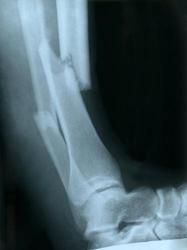

- bone fractures, broken bones, or serious disfigurement.

The following bubble graph shows examples of serious bodily injuries that can elevate a simple battery to an aggravated battery.